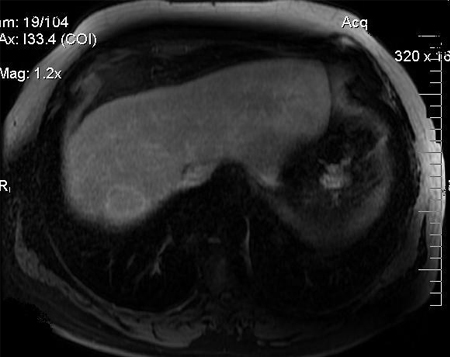

MRI: washout portal phase

From the personal collection of Badar Muneer MD, Florida Hospital Transplant Center, Orlando, FL; used with permission